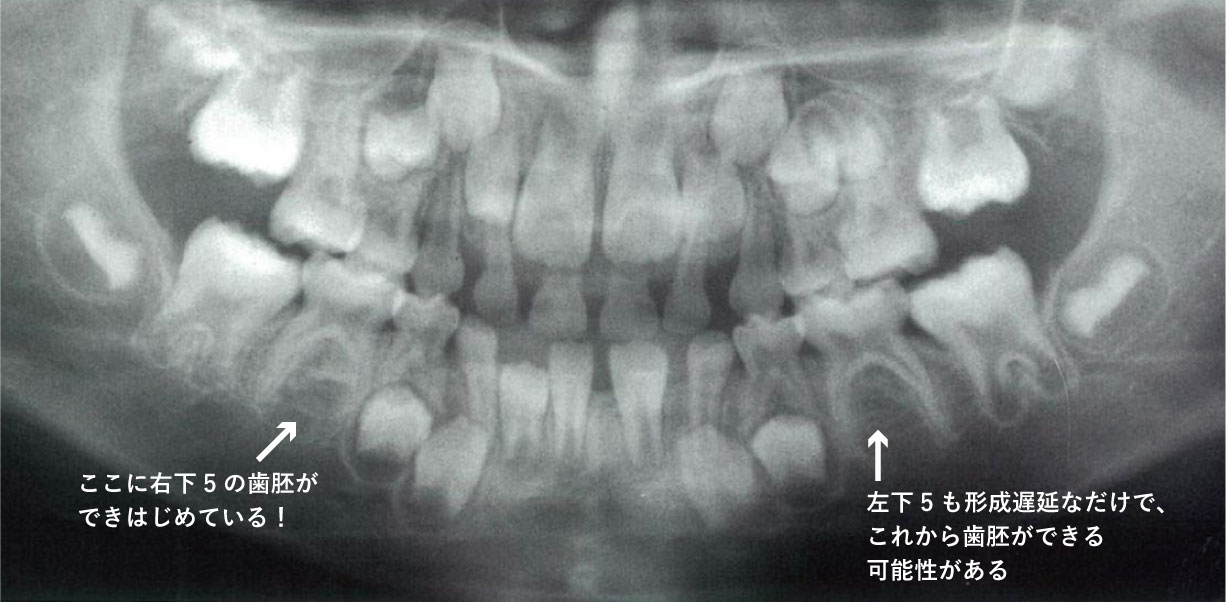

6歳の男児。定期診査を希望して来院した。来院時のエックス線写真を別に示す。

スクリーンショット 2017 01 31 11 14 40

a Hellmanの歯齢はⅢA期である。

b 下顎切歯が1歯不足している。

c 犬歯の歯冠の位置は正常である。

d 下顎第二小臼歯が1歯不足している。

e 第一大臼歯の歯根形成は遅延している 。

正答 b,c

実は、国家試験の正答は間違っています。選択肢の「d 下顎第二小臼歯が1歯不足している。」が、誤答肢になっていますが、これは実は正しいです。パノラマをよく見てみると右下5の歯胚が薄くですが、でき初めています。この感じだと左下5も今後でてくる可能性は十分にあります。

御存知の通り、先天欠如の多い歯種は「8」「5」「2」ですね。それぞれ、「大臼歯」「小臼歯」「切歯」でもっとも遠心にある歯は退化傾向で、先天欠如が多いことで知られています。この問題のパノラマも「5」がその傾向にあり、下顎では歯胚の形成がすごく遅れており右下5のみ確認できます。上顎では左上5が正常に発生していますが、やはり右上5の歯胚は確認できません。

よって、本当はこの「d 下顎第二小臼歯が1歯不足している。」は微妙な選択肢で、最近の感じだと削除かこの選択肢も丸になる流れになると思います。クレームがついてもきちんとした反論はできないかと思わます。(一応、この内容は、大学の小児歯科の先生に確認とれていますし、ANSWERでは画像所見の欄にのみ指摘されています。)